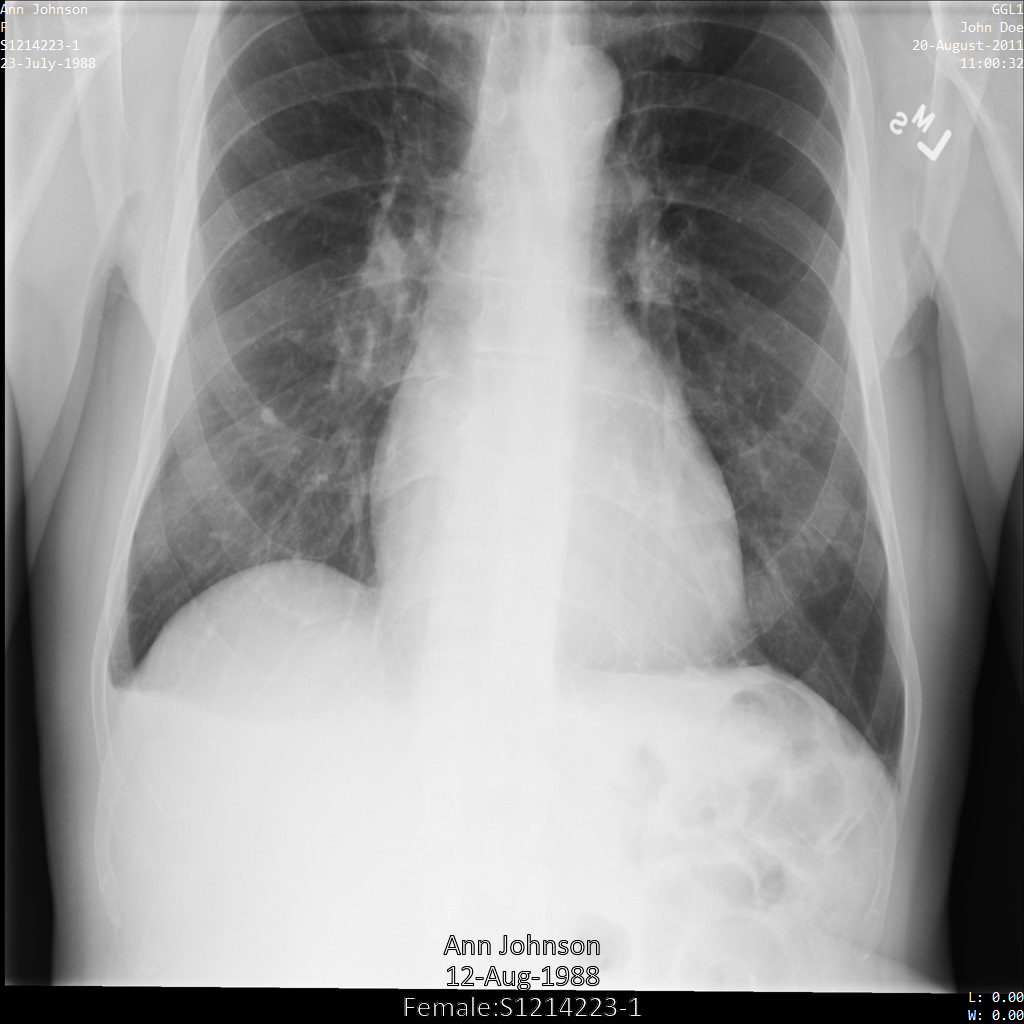

Chacune des sections suivantes fournit des exemples d'anonymisation de données DICOM à l'aide de différentes méthodes. Une sortie de l'image anonymisée est fournie avec chaque échantillon. Chaque exemple utilise l'image d'origine suivante comme entrée :

Vous pouvez comparer l'image de sortie de chaque opération d'anonymisation à cette image d'origine pour voir les effets de l'opération.

L'image suivante montre une radiographie non masquée d'un patient :